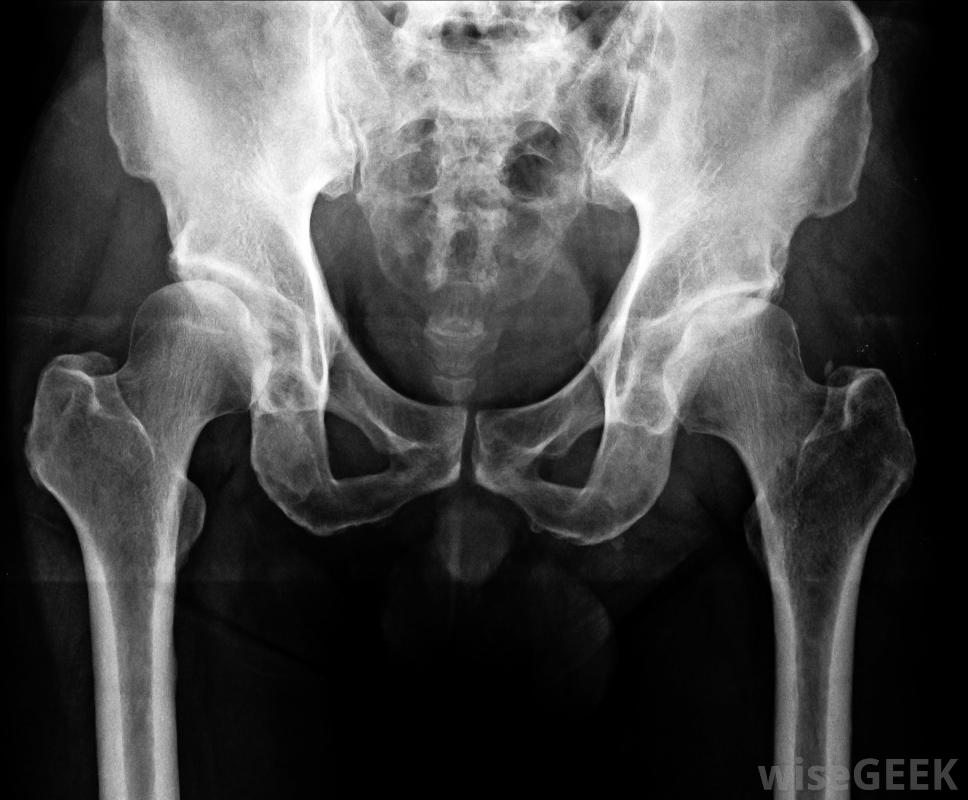

半骨盆切除术是一种外科手术,其中一条腿和一部分骨盆被切除。半骨盆切除术的范围可能会有所不同,有些手术需要切除一半的骨盆,而另一些手术则需要切除少于一半的骨盆。这种手术对病人来说是非常创伤的,是最后的治疗手段;换...

半骨盆切除术是一种外科手术,其中一条腿和一部分骨盆被切除。半骨盆切除术的范围可能会有所不同,有些手术需要切除一半的骨盆,而另一些手术则需要切除少于一半的骨盆。这种手术对病人来说是非常创伤的,是最后的治疗手段;换言之,当外科医生建议进行半骨盆切除术时,他或她认为这对患者是必要的。

在某些情况下,外科医生可以进行内部半骨盆切除术,也就是所谓的"保肢"手术。在这种情况下,部分骨盆被切除,但肢体完好无损,外科医生可以植入人工关节或假体。手术后患者的功能水平可能会有所不同,有些病人的肢体完全丧失了功能,而另一些病人可能还能保留一些功能,外科医生也需要监控这个部位,以防需要进行完全截肢